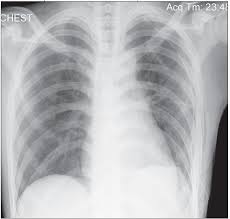

This website is designed primarily as an educational resource. Consult a doctor for medical advice. Catamenial pneumothorax is a condition of air leaking into the pleural space occurring in conjunction with menstrual periods (catamenial refers to menstruation), and or during ovulation, caused by the abnormal growth of endometrial tissue in the membrane surrounding the lung and diaphragm. Oct 09, 2019 · pneumothorax or a collapsed lung, is a lung condition in which the lung(s) has been injured by infection, trauma, disease, cigarette smoking, and other medical problems. Jul 23, 2021 · pneumothorax (collapsed lung) is an injury to the lung that causes air or gas to build up in the thin layer of tissue that covers the lungs and lines the interior wall of the chest cavity. Doctors treat a pneumothorax or collapsed lung depending upon the cause. A pneumothorax can develop into a collapsed lung. It is not intended to provide medical advice on personal health matters or to guide treatment — which is only appropriately done by a qualified health professional. Pneumothorax can lead to a collapsed or punctured lung. It typically happens when there is a rupture of a small air sac on the outside of the lung. This air pushes on the outside of your lung and makes it collapse. Ultrasound imaging also may be used to identify a pneumothorax. This is when the punctured lung occurs without any exact cause. Depending on the cause of the pneumothorax, a second goal may be to prevent recurrences. Ultrasound imaging also may be used to identify a pneumothorax. Jul 23, 2021 · pneumothorax (collapsed lung) is an injury to the lung that causes air or gas to build up in the thin layer of tissue that covers the lungs and lines the interior wall of the chest cavity. A pneumothorax can be caused by: A pneumothorax can develop into a collapsed lung. Pneumothorax Pulmonary Disorders Merck Manuals Professional Edition Pneumothorax Pulmonary Disorders Merck Manuals Professional Edition from www.merckmanuals.com